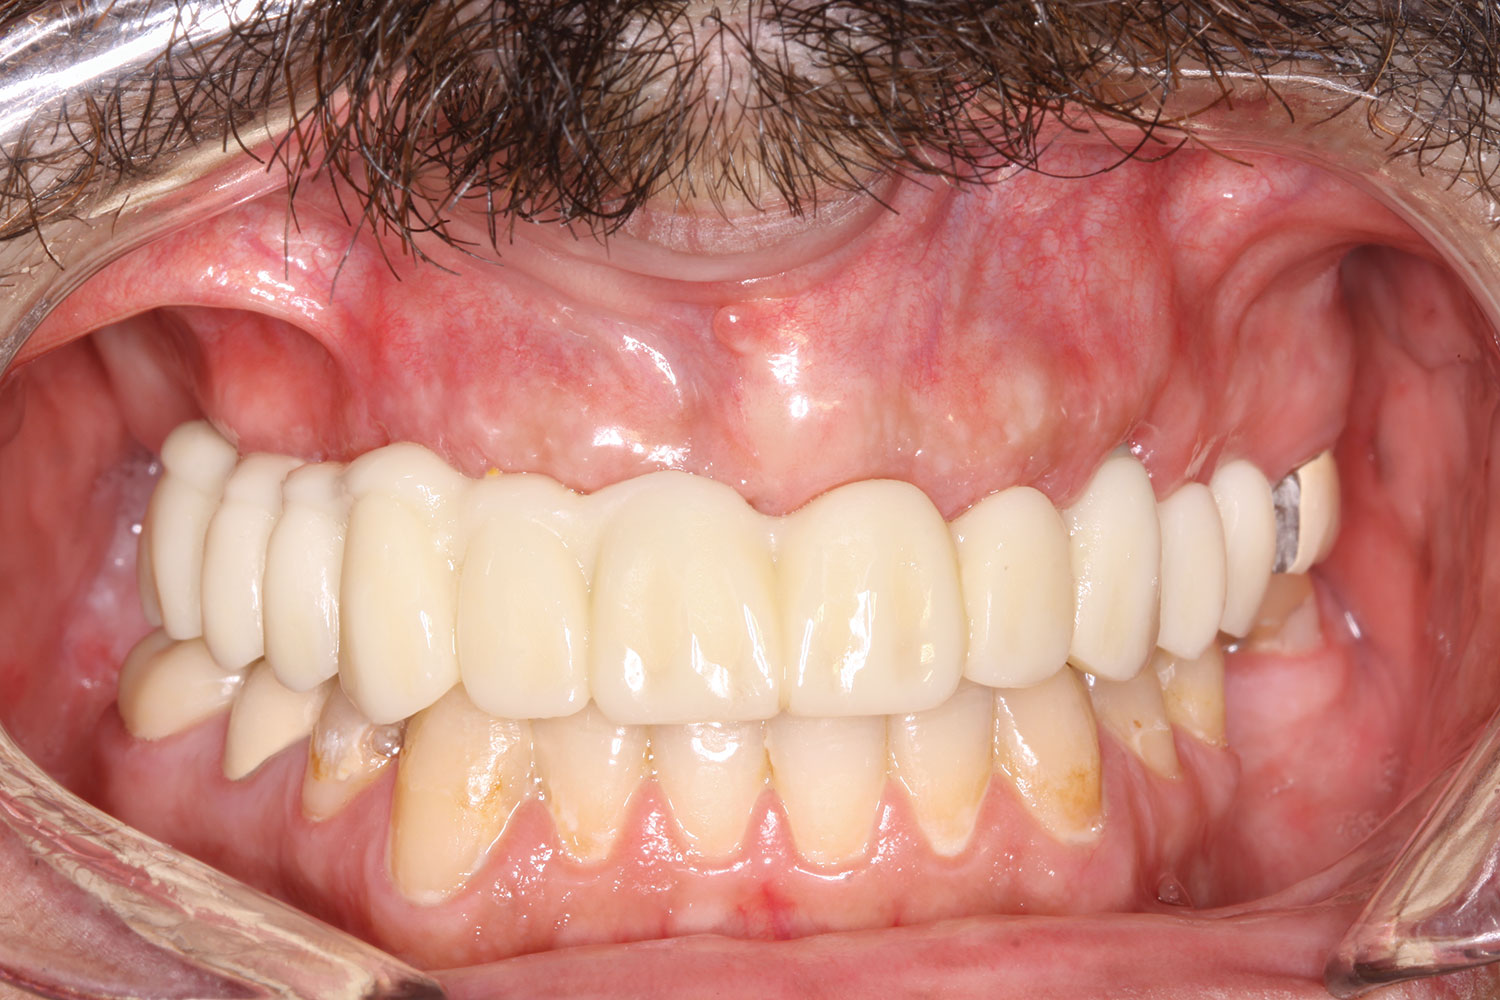

Case 2

A 60-year-old female patient presented with many periodontally and restoratively hopeless teeth that severely compromised esthetics and function and were inadequate to retain a maxillary restoration. She declined to advance into a full maxillary denture or partial denture. Existing maxillary teeth included Nos. 2 and 4 through 14 (Figure 9 and Figure 10). The opposing dentition was stable. The patient was in good health with no allergies to medication.

At the initial visit, a panoramic x-ray (Figure 11) and periapical x-rays were taken. The patient was photographed to capture her full face and shoulders, and a digital scan of the maxillary dentition was obtained. This file was electronically sent to the implant company to complete the VSD.

The prosthesis fit precisely on the multi-unit abutments, and multi-unit screws were used to secure the prosthesis in place at 20 Ncm (Figure 18 through Figure 20). The screw-access holes were filled, and the patient was instructed on dietary restrictions and adherence to a soft diet. Instructions for oral hygiene were given, and the patient was advised to use a water flosser daily. Analgesics included ibuprofen 800 mg, and for antibiotics, amoxicillin 500 mg three times a day was prescribed.

Postoperative x-rays documented the full seating of the prosthesis on the multi-unit abutments (Figure 21 and Figure 22). The patient returned at 1 week postoperatively for a follow-up visit and to review home care. She remarked that the restoration was comfortable and that she was free of discomfort and extremely pleased with the makeover she received in one day.